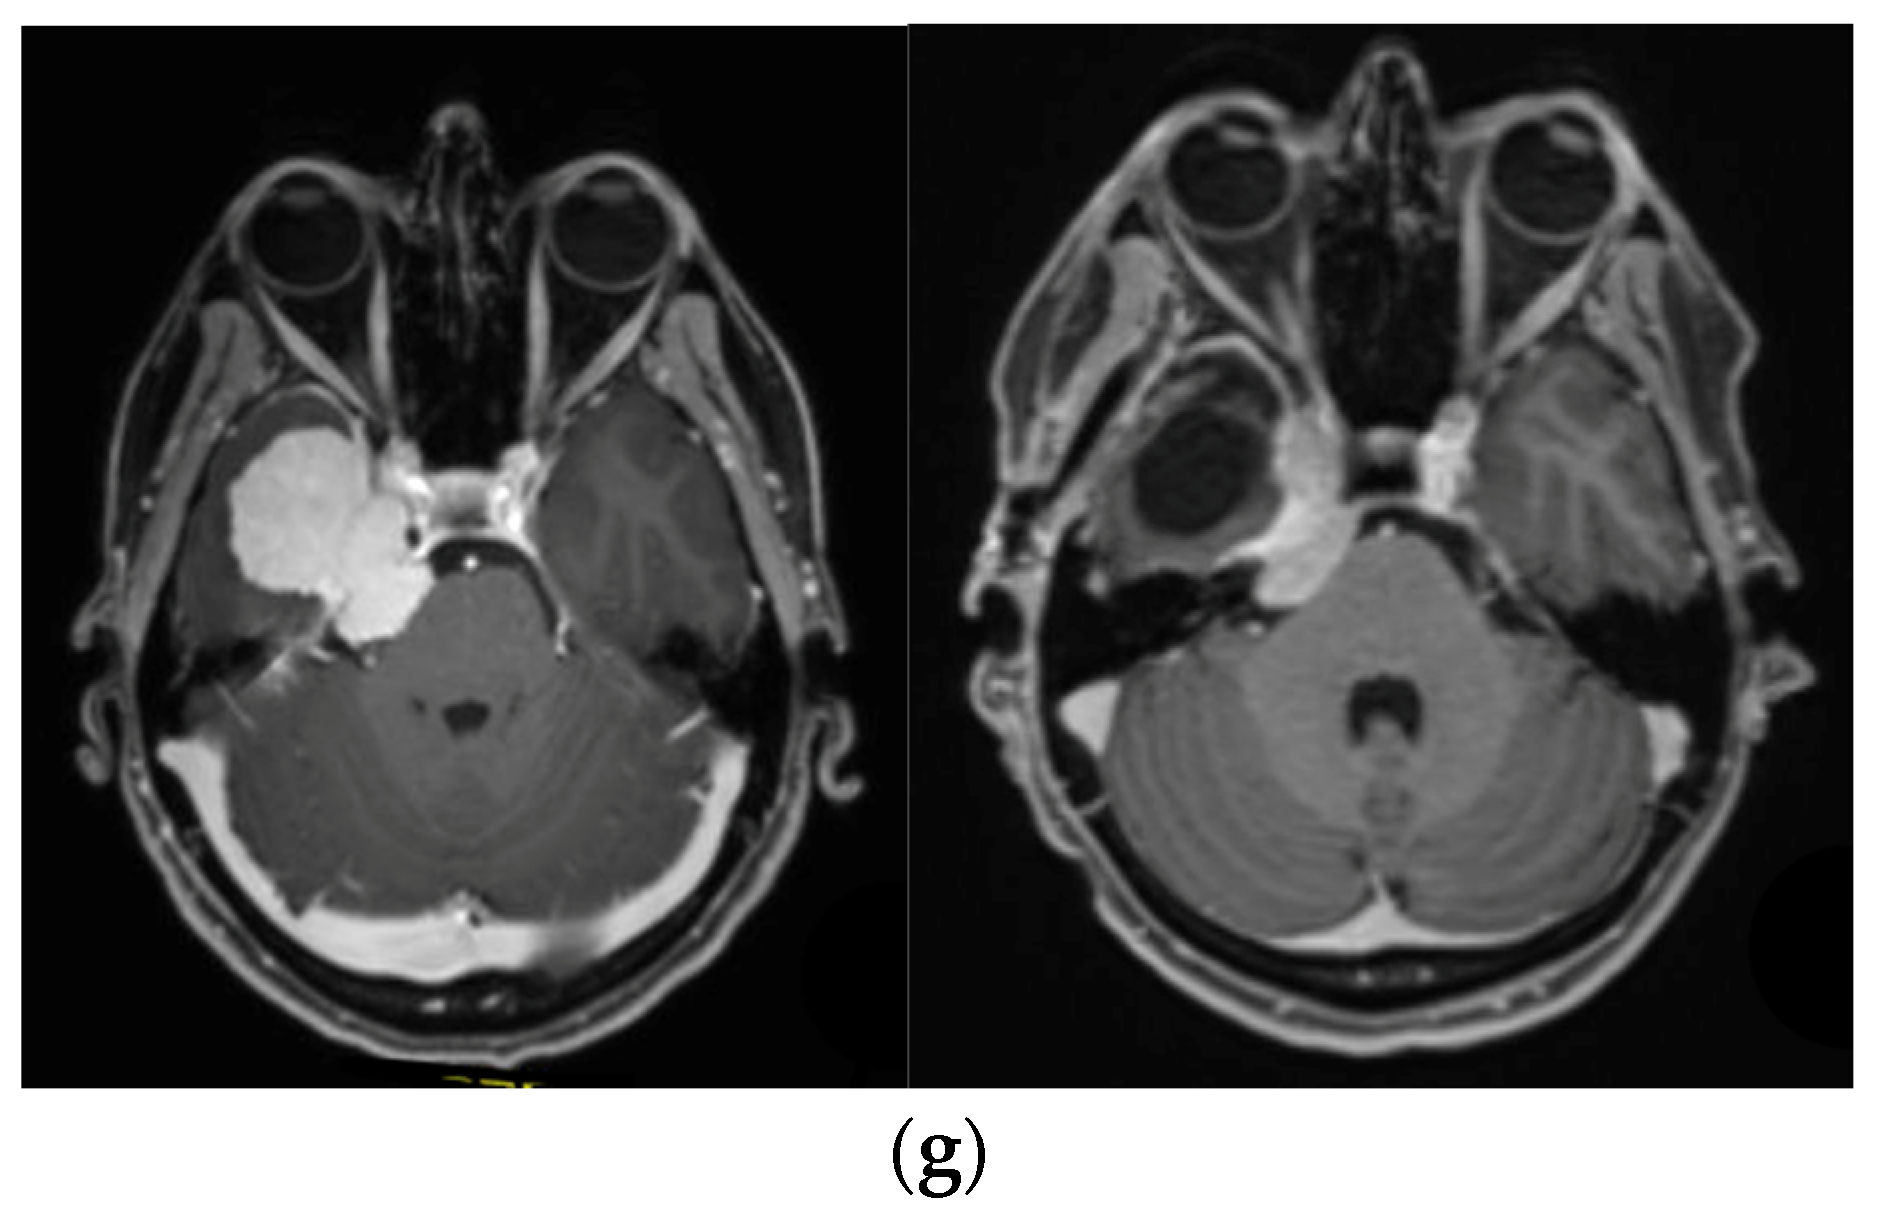

—right optic tract: mean dose unsafe, max. dose safe. (i) Comparison of pre- and 3 months postoperative MRI for stereotactic radiation planning. The residual tumor was finally treated with hypofractionated radiotherapy (5 × 5 Gy).